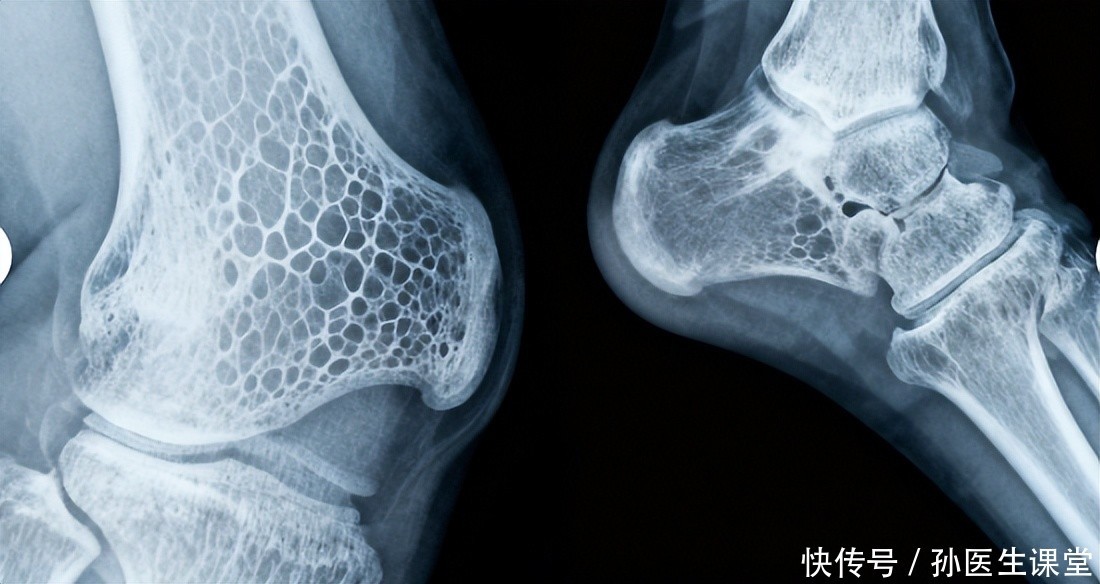

二、轻微外力就容易受伤,骨折或频发骨质疏松使骨骼变得脆弱,即便是平时的小磕碰、轻微摔倒,也可能引发手腕、髋关节或脊椎骨折。临床数据显示,超过60岁的老人,轻微摔倒导致骨折的几率明显上升。一位医生曾比喻:“骨折如同干枯的竹子,稍加弯曲就容易断裂。”当身体出现这种“轻微受力即伤”的迹象时,应当提高警惕,及时做骨密度检查,并在医生指导下采取干预措施。